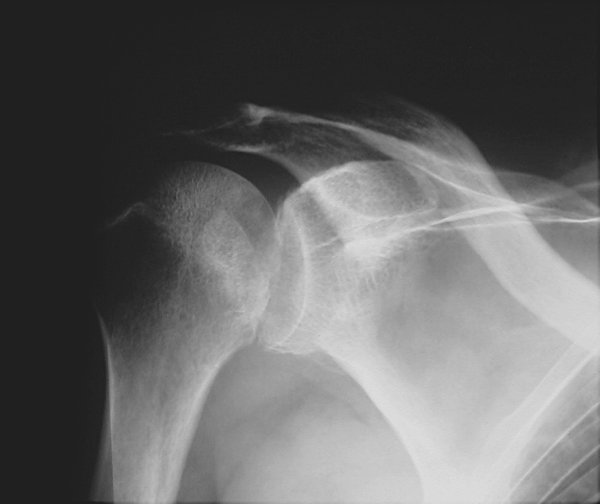

Return to Posterior Dislocation (Humerus)